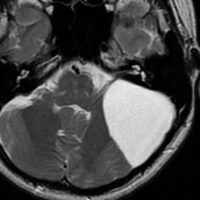

前の例より少し大きいものです。1歳4ヶ月までは,のう胞が増大しましたがその後は同じ大きさで経過しました。